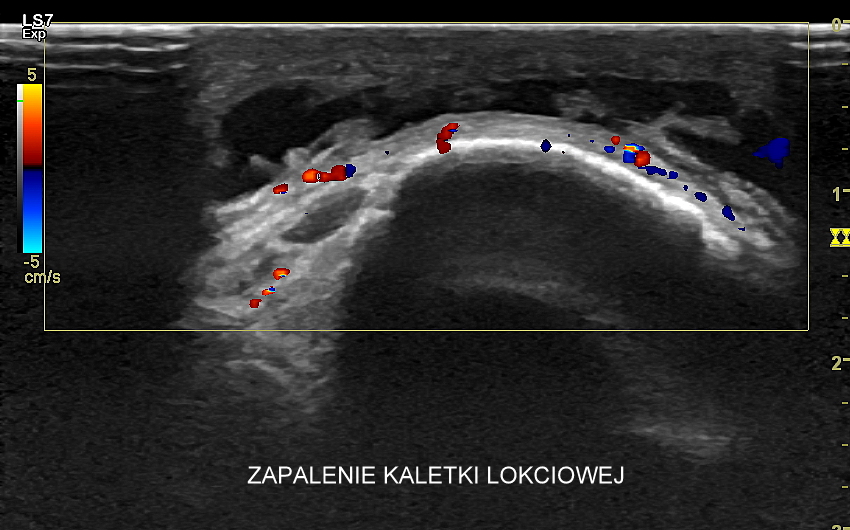

W obręczy barkowej i w kończynie górnej najczęściej spotykane są różnorodne urazy oraz zwyrodnienia w obrębie stawu barkowego związane z pracą, sportem i aktywnością fizyczną; urazy mięśni i ścięgien; zapalenia w tkance podskórnej i żyłach kończyny; poza tym wysięki i zapalenia w zakresie kaletek i pochewek ścięgnistych przedramienia oraz w stawie łokciowym; a także zespoły neuropatyczne związane z uszkodzeniami lub usidleniami nerwów (np. nerwu łokciowego i pośrodkowego); zapalenia nadkłykcia przyśrodkowego oraz nadkłykcia bocznego kości ramiennej; jak również różnego rodzaju ciała obce (np. drzazgi, opiłki metalu, drobiny szkła). Badanie USG jest przy tym kluczową metodą diagnostyczną ukierunkowująca dalsze postępowanie lecznicze.